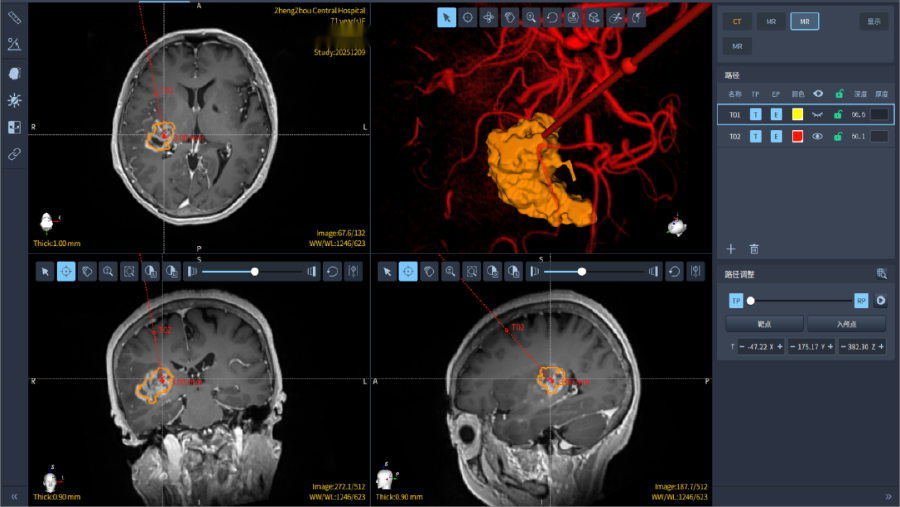

術(shù)前,醫(yī)療團隊依托患者 CT、磁共振影像數(shù)據(jù),通過計算機系統(tǒng)完成三維手術(shù)規(guī)劃,精準(zhǔn)設(shè)計穿刺路徑,避開顱內(nèi)大血管及重要神經(jīng)組織,確保手術(shù)安全。

術(shù)前精準(zhǔn)設(shè)計穿刺病變位置、避開大的腦血管

手術(shù)過程中,神經(jīng)外科手術(shù)機器人憑借亞毫米級定位精度,如同為手術(shù)配備了"GPS 導(dǎo)航系統(tǒng)"與"穩(wěn)定機械臂",精準(zhǔn)引導(dǎo)穿刺器械沿預(yù)設(shè)路徑抵達腦深部病變區(qū)域,成功獲取病變組織樣本。